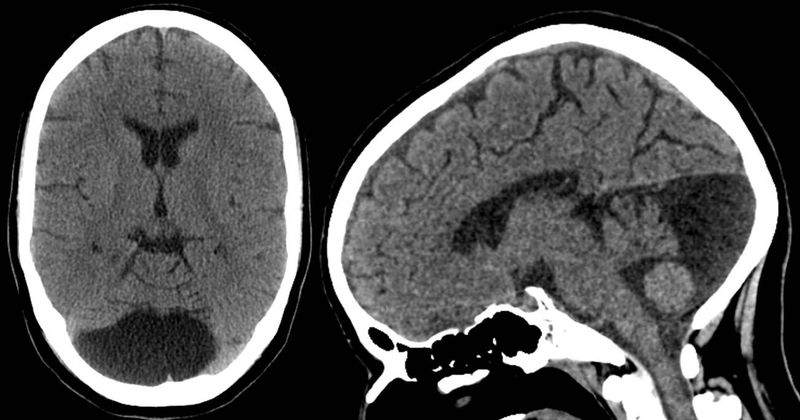

Để hiểu rõ hơn về u nang màng nhện ở thai nhi, trước tiên ta cần biết thế nào là nang màng nhện? Về mặt mô học, nang màng nhện là một khối choáng chỗ lành tính chứa đầy dịch não tủy tại hệ thần kinh trung ương. Hấu hết các trường hợp là tổn thương lành tính, có thể nằm ở nội sọ (đa số nằm ở vị trí trên lều), tủy sống hoặc quanh dây thần kinh. Thông thường khoảng 50% các nang màng nhện xuất hiện ở hố sọ giữa, 11% là ở góc cầu - tiểu não, 8-9% ở vùng yên, ống sống.

Nang màng nhện ở thai nhi là một nang đơn độc, chưa nước, dịch não tủy và thường xuất hiện ở não hoặc tủy sống. Hầu hết các trường hợp là dạng tổn thương lành tính, hiếm khi liên quan đến các bất thường nhiễm thể thường gặp trong lúc mang thai như NST 13, 18, 21 hay bất thường về não khác, chỉ có 2-5% có liên quan đến chấn thương hoặc nhiễm trùng (nang thứ phát). Nang màng nhện ở thai nhi được chia ra giới hạn bởi 2 lớp là: Màng trong và màng ngoài. Các lớp màng này có thể được tạo ra bởi tế bào thần kinh đệm, tế bào màng ống nội tủy hay lá của tế bào màng nhện.

Khi được chẩn đoán nang màng nhện thai nhi, rất nhiều sản phụ vô cùng lo lắng và sợ ảnh hưởng đến thai nhi sau này. Tuy nhiên nang màng nhện đa số thường lành tính, bé có thể phát triển bình thường mà không bị ảnh hưởng gì đến hệ thần kinh, phát triển tâm vận của trẻ. Trong một số trường hợp đặt biệt, nang màng nhện ở thai nhi phát triển quá nhanh, quá lớn, gây chèn ép, tăng áp lực nội sọ hay có một số triệu chứng thì sẽ có chỉ định phẫu thuật. Phương pháp được cân nhắc trước hết, dựa trên triệu chứng, vị trí và kích thước của nang là phương pháp phẫu thuật, tạo đường dẫn đến các khoang hấp thụ dịch nang.